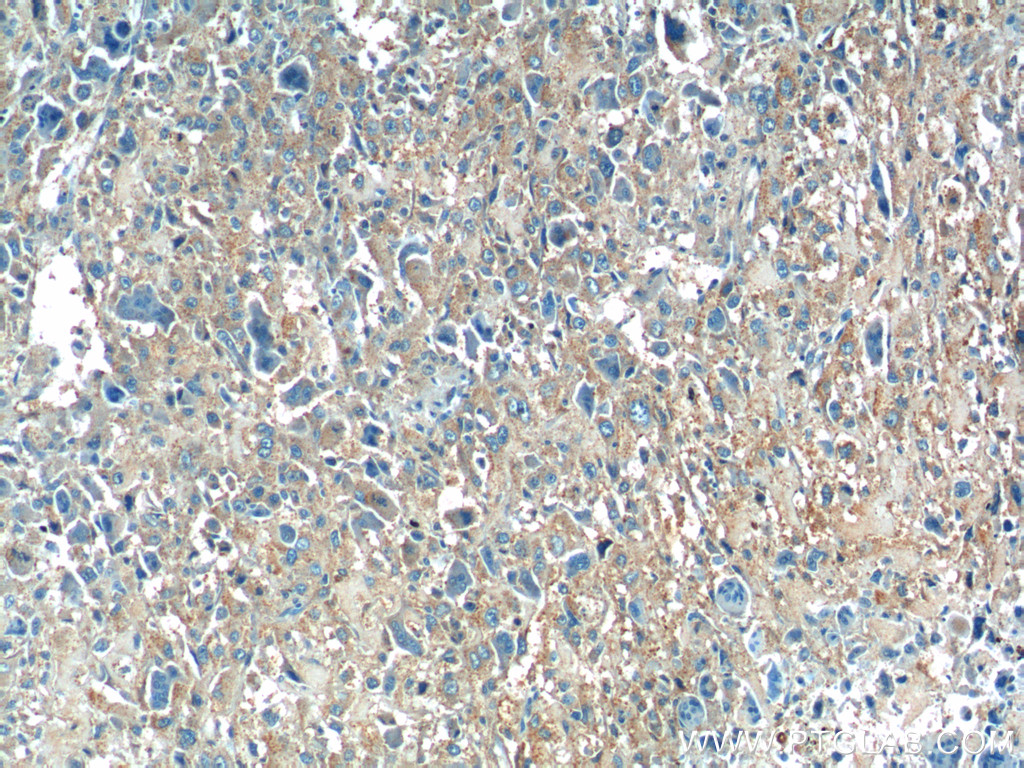

| Positive IHC detected in | mouse testis tissue, human osteosarcoma tissue, human testis tissue, rat testis tissue, mouse kidney tissue Note: suggested antigen retrieval with TE buffer pH 9.0; (*) Alternatively, antigen retrieval may be performed with citrate buffer pH 6.0 |

| Immunohistochemistry (IHC) | IHC : 1:50-1:500 |

23418-1-AP targets Osteocalcin/OCN in IHC, IF/ICC, FC (Intra), ELISA applications and shows reactivity with human, mouse, rat samples.